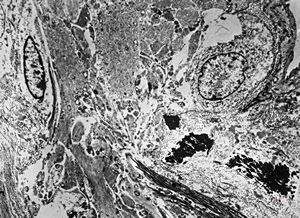

F,49y. | purulent meningitis- meningococcal v.s.